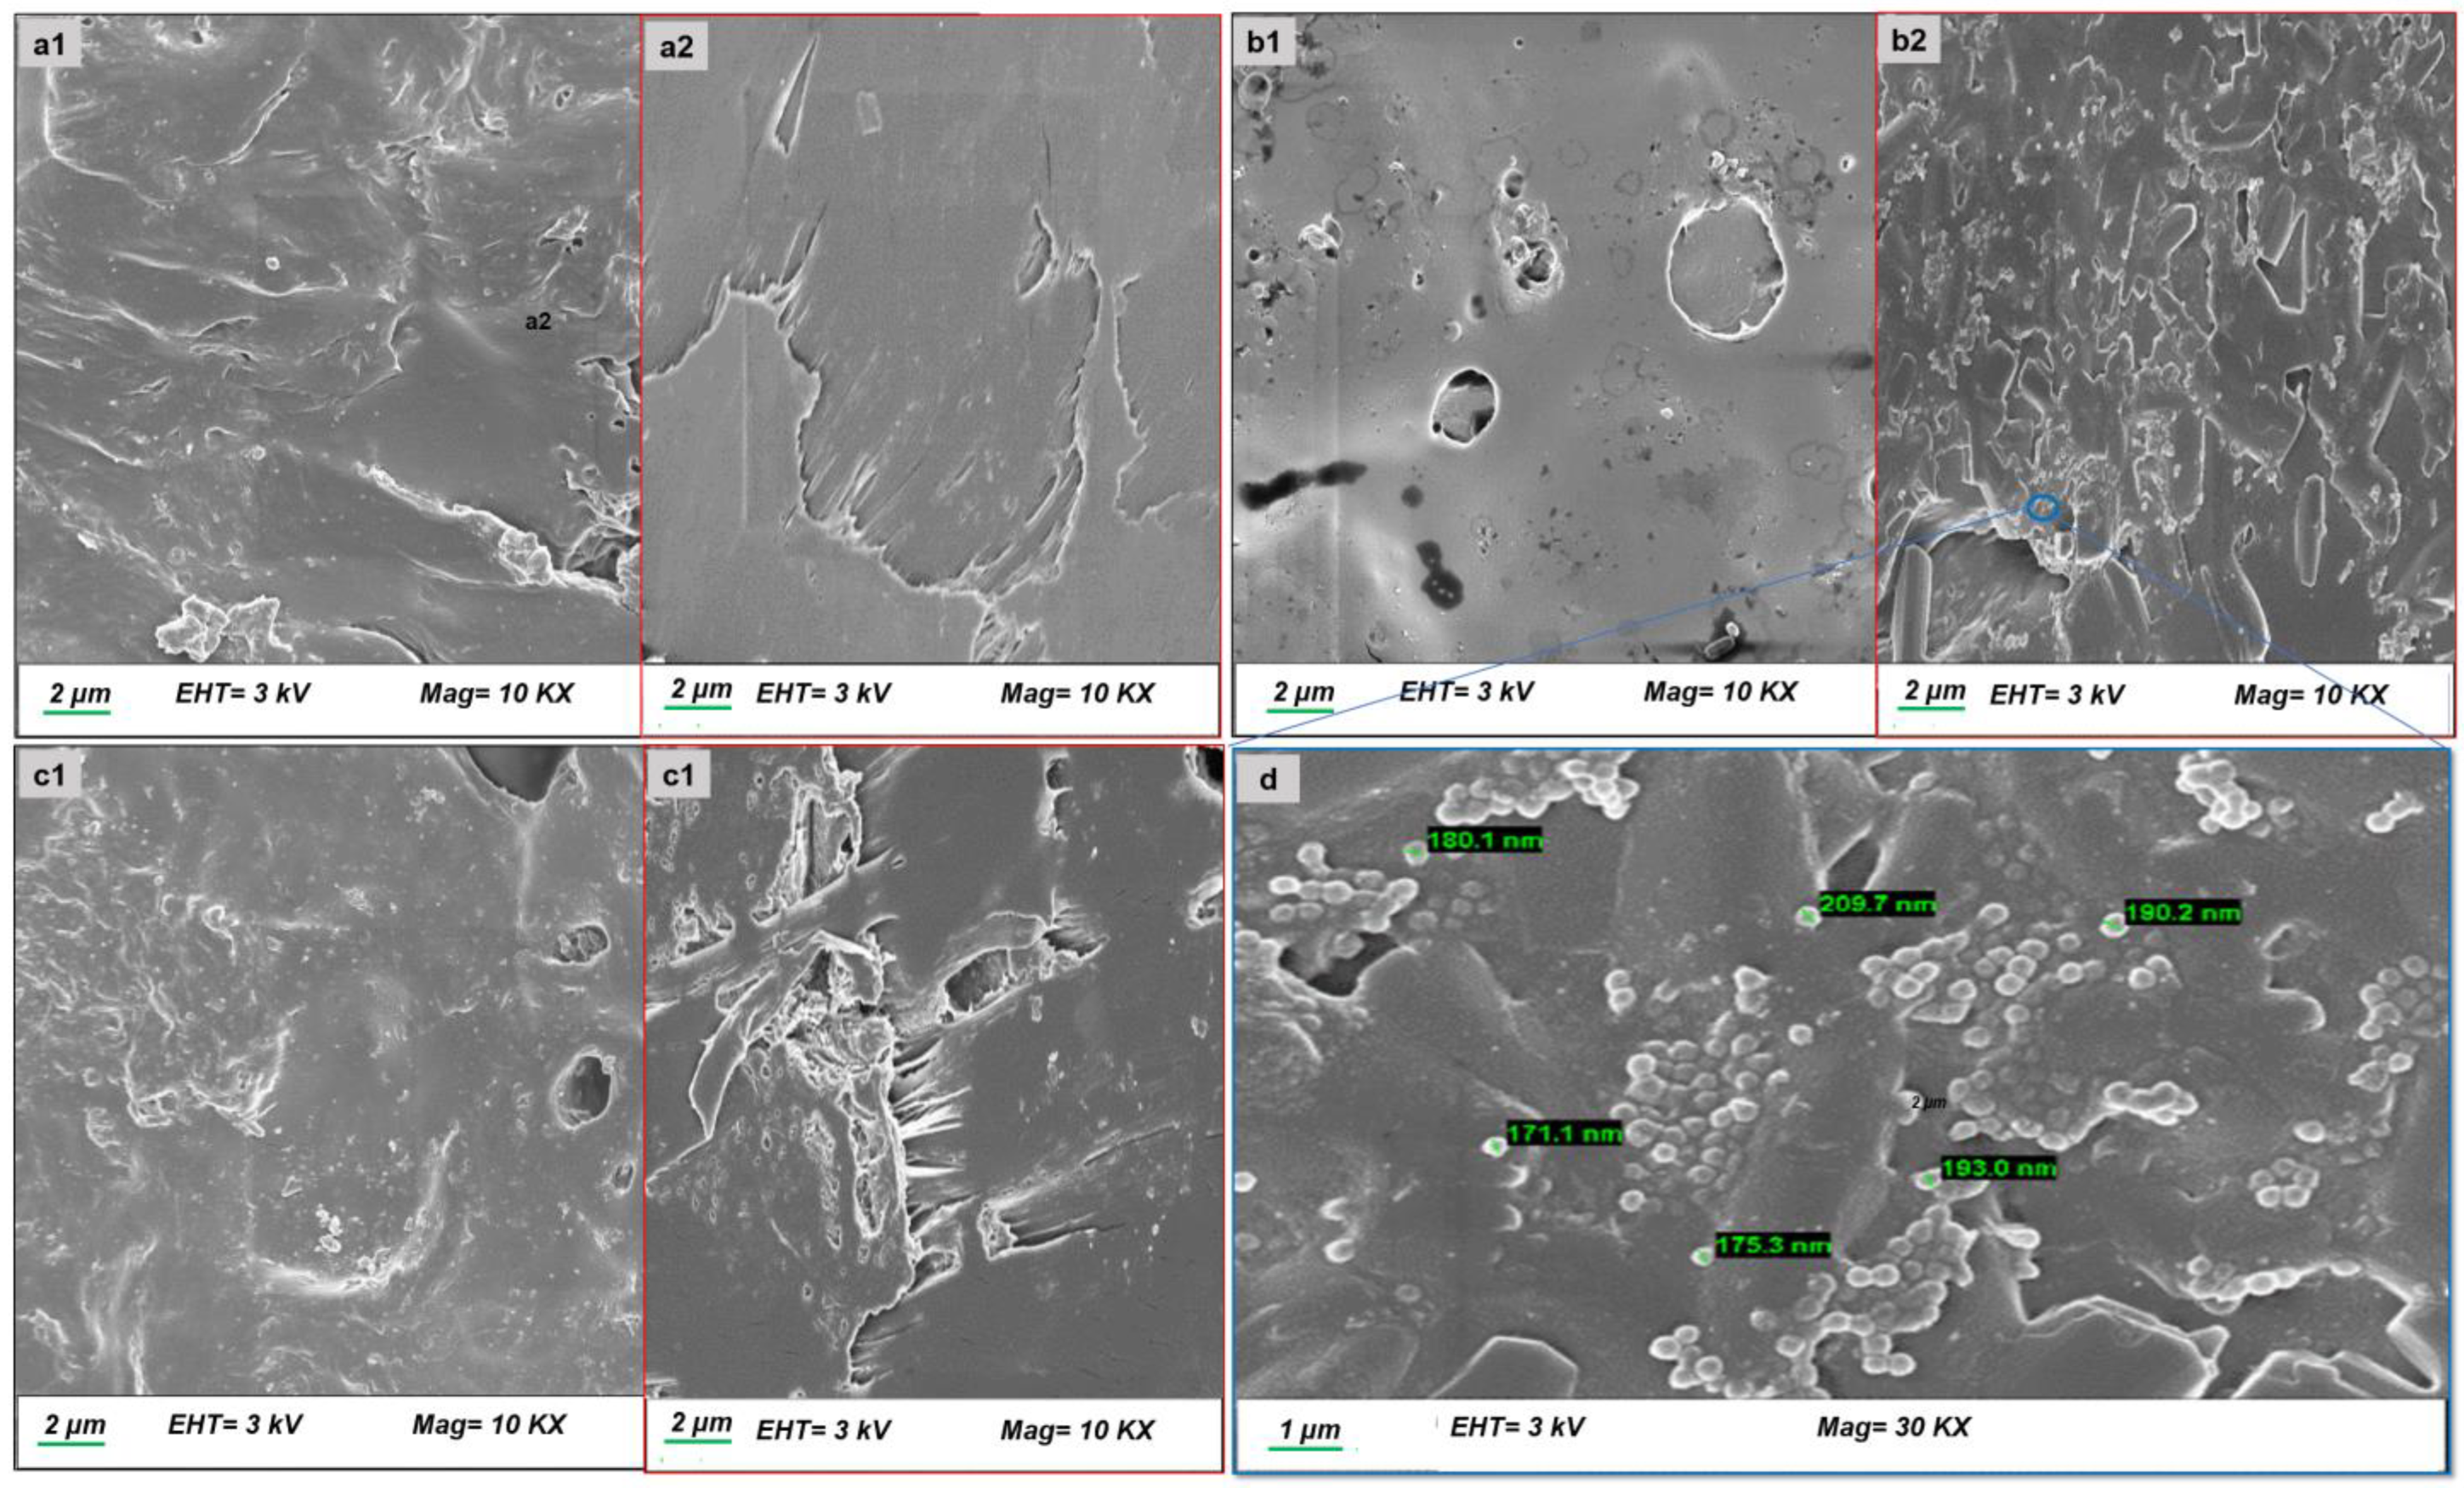

3.2.3. Morphological Analysis

Morphological Analysis